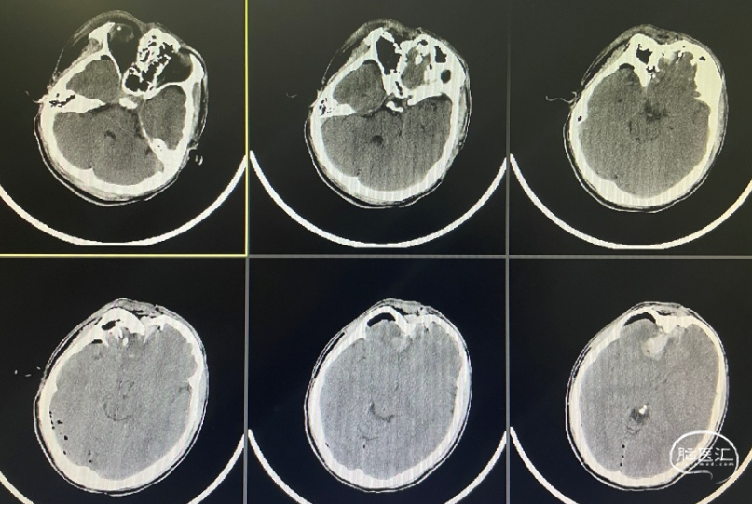

监测有道丨开放性颅脑外伤伴前额部粉碎性骨折一例报道颅脑创伤神经

图片尺寸752x505